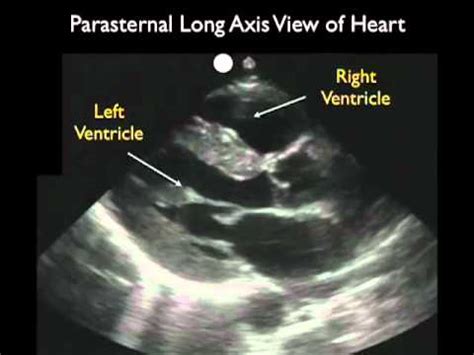

Alright guys, let’s dive deep into the echocardiogram parasternal long axis view probe position . This is a fundamental view in echocardiography, and getting it right is crucial for a clear and accurate cardiac assessment. Think of it as the foundation for understanding how your patient’s heart is functioning. We’re talking about visualizing the left ventricle, the mitral valve, the aortic valve, and the left atrium in a beautiful, side-by-side profile. When you nail this view, you’re setting yourself up for success in diagnosing a whole range of conditions, from valve issues to chamber dilation. It’s the first step, the most important step, and frankly, one of the most rewarding to master. We’ll break down the exact placement, the common pitfalls, and how to troubleshoot to get that perfect image every single time. So grab your ultrasound probe, and let’s get this show on the road!

So, you want to master the parasternal long axis view ? This is where the magic happens in echocardiography, folks! This view gives us an incredible look at the left side of the heart. Imagine peering into the heart from the side, seeing the major players lined up perfectly. We’re talking about the left ventricle (LV) , that powerhouse chamber, the mitral valve controlling blood flow into the LV, the aortic valve directing blood out to the body, and the left atrium (LA) receiving blood from the lungs. Getting this view correctly is absolutely essential for assessing LV size and function, detecting mitral regurgitation or stenosis, evaluating the aortic valve, and spotting any enlargement of the left atrium. It’s like getting the money shot of the heart’s pumping action. Without a solid parasternal long axis view, any other echo assessment will be incomplete, possibly even misleading. We’ll guide you through the precise steps to achieve this view, covering everything from where to place the transducer to how to angle it for the best visualization. We’ll also touch on common mistakes and how to fix them, because let’s be real, nobody gets it perfect on the first try, and that’s totally okay! This section is all about building your confidence and competence in one of the most important echocardiographic views.

Let’s chat about why the parasternal long axis view is such a big deal in echocardiography. You might be wondering, “Why this specific view?” Well, guys, it’s all about getting a comprehensive picture of the heart’s most critical components. This view provides a longitudinal or ‘long’ axis view of the left ventricle, allowing us to see its shape, size, and how it’s contracting. We can directly visualize the mitral valve leaflets opening and closing, and assess for any abnormalities like thickening, prolapse, or regurgitation. Similarly, the aortic valve comes into clear view, enabling us to check for stenosis (narrowing) or regurgitation (leakage). The left atrium is also beautifully displayed, so we can measure its size and determine if it’s enlarged, which can be a sign of various heart conditions. Furthermore, the interventricular septum and the posterior wall of the left ventricle are clearly visible, allowing for assessment of wall thickness and motion abnormalities. This view is often the starting point for many echocardiographic examinations because it offers such a wealth of information about the left heart. It’s fundamental for diagnosing conditions such as hypertrophic cardiomyopathy, dilated cardiomyopathy, valvular heart disease, and even helps in evaluating the impact of hypertension on the heart. It’s like having a blueprint of the heart’s main pumping system laid out right in front of you. So, the ‘why’ is simple: it gives us a clear, consistent, and highly informative window into the functional anatomy of the left heart, making it indispensable for accurate diagnosis and management of cardiovascular diseases.